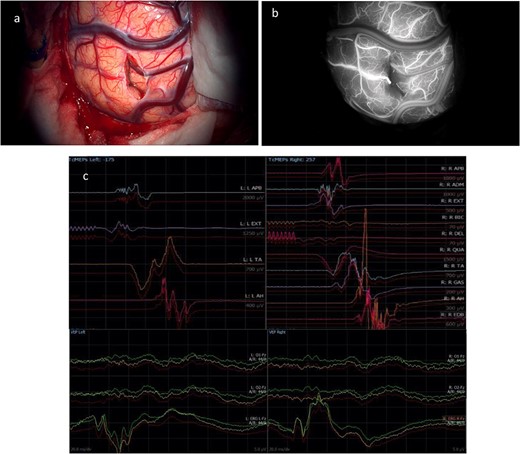

Intraoperative neurophysiology monitoring (IONM) was performed throughout the case using two subdural strips, placed over the motor and occipital cortices following craniotomy. At the end of the procedure (Fig. 4a), CST was identified with subcortical stimulation at 8 mA, and both visual and motor evoked potentials (VEPs and MEPs) were stable (Fig. 4c). An external ventricular drain (EVD) was left in place. Indocyanine green angiography demonstrated no injury to nearby vascular structures (Fig. 4b).

(a) Final microscopic view of the brain surface under bright light: the entry point of the operative corridor is visible at the level of the cortex, in the sulcus. (b) Microscopic final intraoperative view of the brain surface after indocyanine green injection: the vessels are represented without evidence of flow reduction or interruption. (c) Final screenshots of the intra-operative neurophysiology monitoring recorded with stable MEPs and VEPs responses (baseline in red).